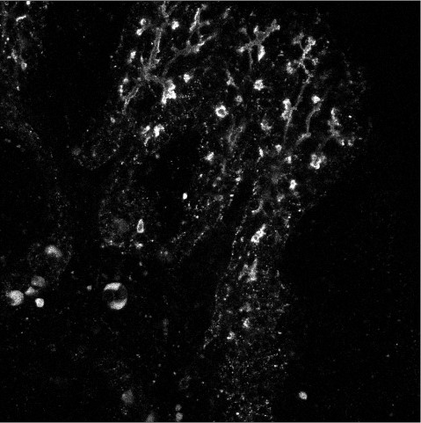

Motivated by the challenging segmentation task of pancreatic tubular networks, this paper tackles two commonly encountered problems in biomedical imaging: Topological consistency of the segmentation, and expensive or difficult annotation. Our contributions are the following: a) We propose a topological score which measures both topological and geometric consistency between the predicted and ground truth segmentations, applied to model selection and validation. b) We provide a full deep-learning methodology for this difficult noisy task on time-series image data. In our method, we first use a semisupervised U-net architecture, applicable to generic segmentation tasks, which jointly trains an autoencoder and a segmentation network. We then use tracking of loops over time to further improve the predicted topology. This semi-supervised approach allows us to utilize unannotated data to learn feature representations that generalize to test data with high variability, in spite of our annotated training data having very limited variation. Our contributions are validated on a challenging segmentation task, locating tubular structures in the fetal pancreas from noisy live imaging confocal microscopy. We show that our semi-supervised model outperforms not only fully supervised and pre-trained models but also an approach which takes topological consistency into account during training. Further, our approach achieves a mean loop score of 0.808 for detecting loops in the fetal pancreas, compared to a U-net trained with clDice with mean loop score 0.762.